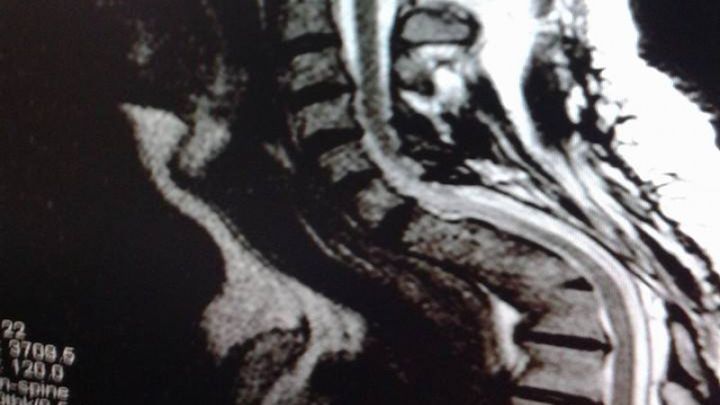

I developed a anneurismal bone cyst and a giant cell tumor on my spinal column . I went through 4 procedures to remove the tumor and cyst . The mass fusion did not hold properly and deformed but still my spinal cord is in good condition. Yes the picture is 100% real.